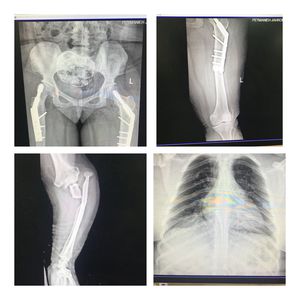

A 40 y/o female who has multiple spontaneity fractures and dwarfism, no deformities in bones, no any other significant medical history , no sign of blue sclera. She had both side bipolar hemi arthroplasty surgery 1 year ago and now the left one has been broken again. The C-xray shows that she has cardiomegaly and multiple ribs Fxs.

I didn’t describe the whole P/E , the pt has Dental displasia , and also she seems to have some early genu varum deformities, and her first bone Fx was at the age of 10 and her sister has the same problems; so now her diagnosis is Osteogenesis imperfecta type 4